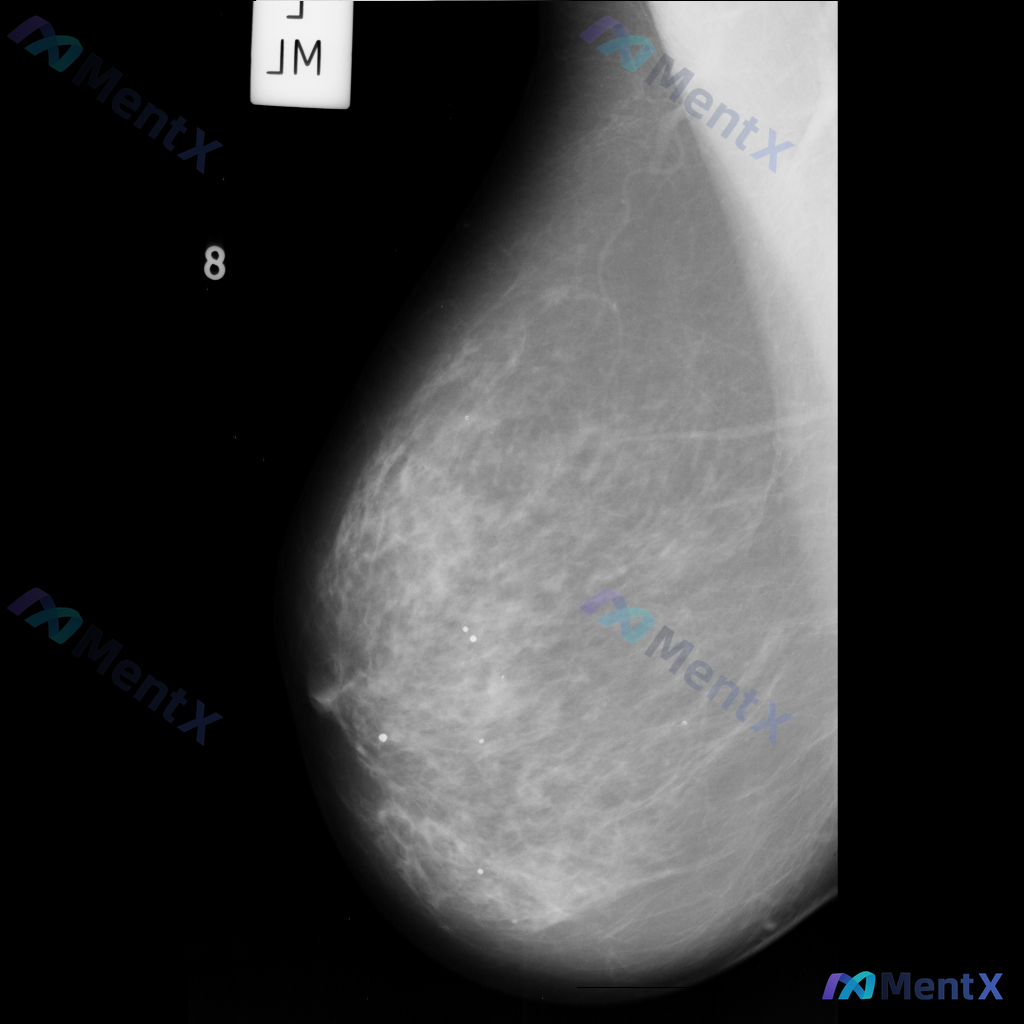

整理到一份乳腺影像的分析资料,想请大家一起讨论看看。 基本信息: - 影像类型:左侧乳腺钼靶内外斜位(MLO) 影像主要表现: 1. 左侧乳腺中上部及外侧可见局灶性结构扭曲 2. 乳腺腺体组织以纤维腺体为主,密度较高,为不均匀致密型(ACR BI-RADS C型) 3. 腺体可见多发斑片状、结节状高...

各位同道好,今天分享一则左乳钼靶病例,影像表现如下: 1. 左乳下方(近乳头区)可见一个边界清晰、形态卵圆形的等/稍高密度肿块影; 2. 左乳中央及下象限腺体局部密度增高和结构紊乱; 3. 散在分布的粗大点状钙化。 上传的钼靶影像编号为mdb083.png,供大家参考。 针对这组表现,你更倾向于哪种...